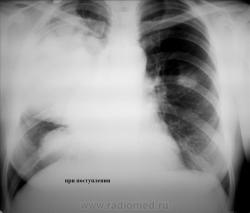

Больная, молодая женщина, алкогольного поведения, поступила в стационар 1 неделю назад, с признаками интоксикации, фебрильной температурой, дыхательной недостаточностью, кровохарканьем в ОАК лейкоцитоз, СОЭ, сдвиг формулы влево, состояние на момент поступления было тяжелое, госпитализирована в хирургическое отделение, с диагнозом тумор правого легкого, легочное кровотечение, по УЗИ печень увеличена-цирротические изменения. Больной проводилась консервативная терапия, массивная антибиотикотерапия, через несколько дней переведена в терапевтическое отделение, состояние больной несколько улучшилось, температура субфебрильная, кашель с мокротой слизисто-гнойного характера, много. Произведена контрольная рентгенография ОГК, планируется проведение ЛТ. Уважаемые коллеги помогите разобраться со снимками, абсцедирующая пневмония в верхней доле правого легкого, может ли здесь иметь место и тумор правого легкого? есть и инфильтративная тень и в верхней доле левого легкого? что это? Простите за качество снимков.

Инфильтрация явно не пневмоническая-гомогенность и четкость контуров говорит против нее.

Кстати, про средостение тоже не забывайте-не исключено, что процесс оттуда идет.Справа формируется уровень жидкости, но не совсем понятный.Второй снимок жестковатый, поэтому тень слева не видна четко.

На мой взгляд, пока данные за абсцедирующую пневмонию. Есть слабоположительная динамика (частичное рассасывание инфильтрата слева). Надо продолжать массивную неспециф. терапию с последующими контролями. DDS с TBC. За онко пока сомнительно, все укладывается в пневмению.

Полисегментарная инфильтративная пневмония с 2-х сторон,с абсцедированием справа в верхнем поле;справа, можно предположить междолевой плеврит с локализацией по главной междолевой щели в базальных отделах( чёткие, очерченные контуры затенения,что нехарактерно для пневмонии).С учётом всей информации, необходимо дифференцироватьс эмпиемой плевры.Данных за патологию средостения не нахожу.

Пока, как рабочая версия, скиалогически билобарная вневмония по типу крупозной с полость деструкции в верхней доле.

С верхнедолевой справа - без вопросов, как и с деструкцией. А вот базально...мне больше импонирует мысль АЛМО по поводу осумкованого плеврита, и знаете, что наводит на эту мысль - полоска просветления между нижним краем затемненной в\доли с затемнением в передне-базальном отделе. если бы это была инфильтрация легочной ткани - этой полоски бы не было, а вот если это коллабированая средняя доля - тогда другое дело и она, эта светлая полоска, вполне обьяснима. Слева - отсев пневмонии в виде овального инфильтрата. Как такое предположение?